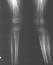

X-Ray Set 3. Post-Op, Neutral alignment

X-Ray Set 4. 3 Months post Surgery , Left 6* Mechanical axis